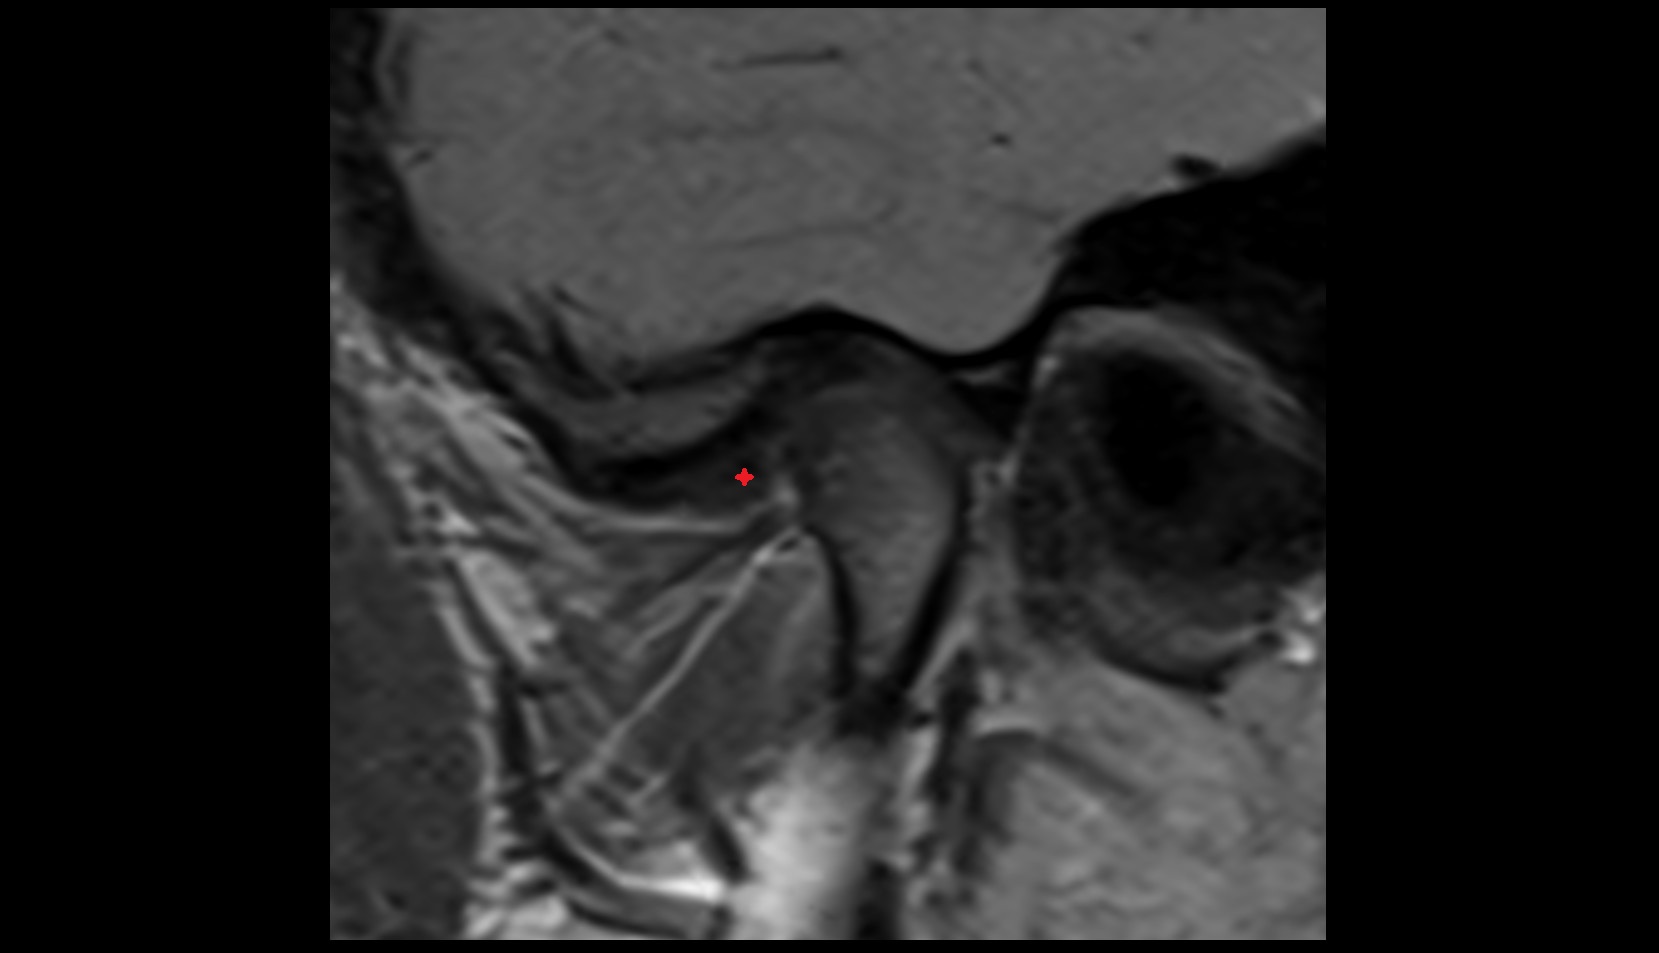

- Temporomandibular joint

- Articular disc of temporomandibular joint

- Articular eminence

- Mandibular condyle

- Mandibular fossa